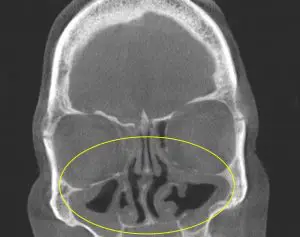

Physical Exam: Clinical and physical exam revealed a component of pressure and discomfort overlying both maxillary(cheek) and forehead(frontal) sinuses. Nasal exam revealed significant congestion and redness(erythema), consistent with inflammation. An in-office CT Sinus was then performed revealing diffuse sinusitis at all sinus cavities(Pre Treatment). This resulted in an accurate diagnosis of bilateral recurrent acute sinusitis as the cause of this patient’s symptoms.

Before:

Summary: Following appropriate medical treatment with a prolonged course of antibiotics and steroids, the patient noted a significant decrease in the symptoms of congestion, sinus pressure, and post nasal drip. The ear pressure had resolved as well. This is evident from the improved sinus drainage noted in the PostTreatment CT Sinus. One can even appreciate the widened surgical sites this patient had created during surgery many years prior. Often times a patient has been treated with traditional courses(7-10 days) of antibiotic therapy without much relief, whereas a slightly longer course with a different antibiotic will be more effective at resolving both recurrent and chronic sinus problems. Short courses of steroids are a key component of sinus treatment as well due to their anti-inflammatory effects. Confirmation of the extent of sinus disease by CT Scan is important before starting patients on prolonged courses of antibiotics, as they are not without side effects. With an accurate diagnosis, proper treatment is provided resulting in improved clinical symptoms.